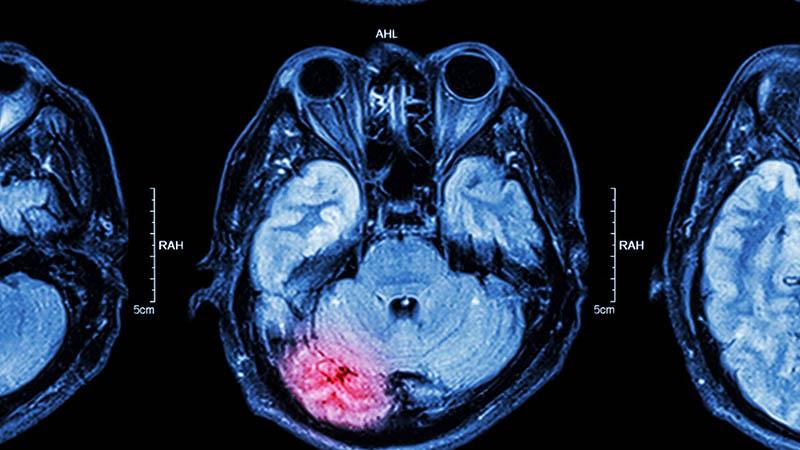

MRI of brain: brain injury

Fighting in Ice Hockey: It’s Time for a Change

Orthopedic surgeons from NewYork-Presbyterian/Columbia’s Center for Shoulder, Elbow and Sports Medicine brought awareness to the dangers of fighting in professional ice hockey. In research published in Frontiers in Sports and Active Living, Translational Sports Medicine, and The Physician and Sports Medicine, doctors addressed the ramifications of fighting in the National Hockey League (NHL) which increases the risk of chronic traumatic encephalopathy and neurobehavioral consequences. Research supports the need to set a precedent of protecting players by limiting unnecessary injuries and hits to the head.